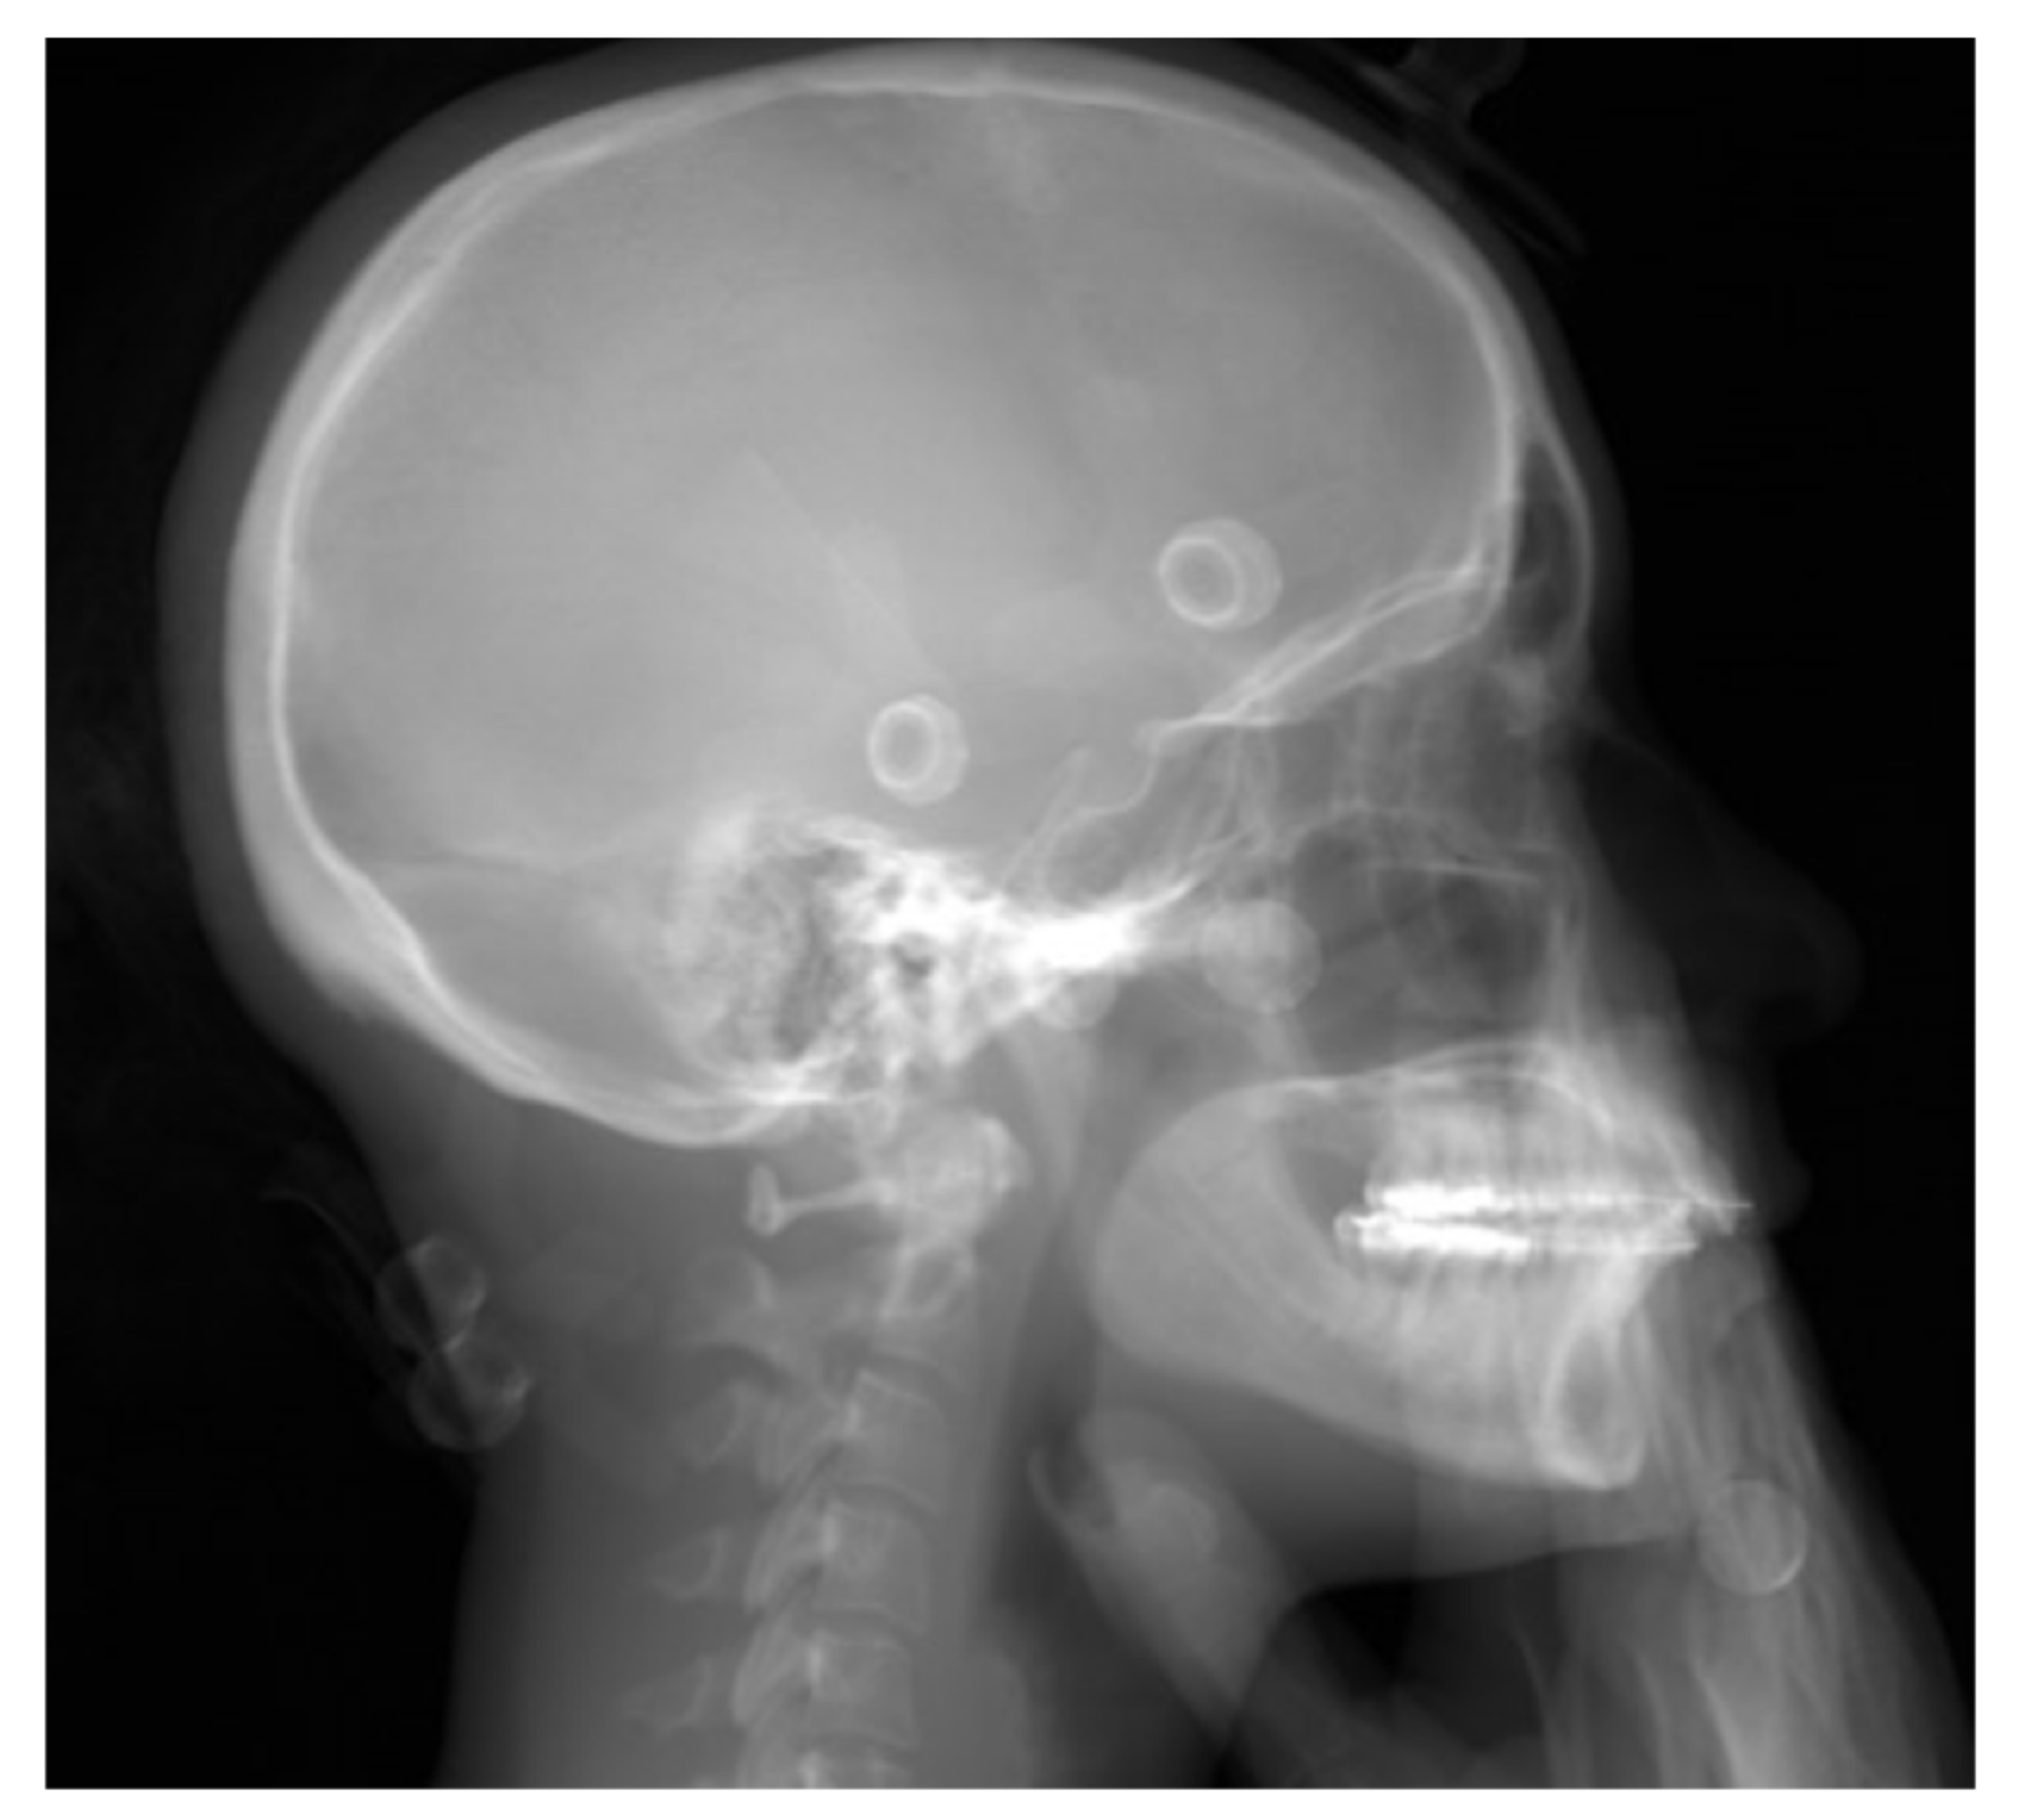

2.2. Image Acquisition

2.3. Comparison of BPXR and Lateral Cephalograms